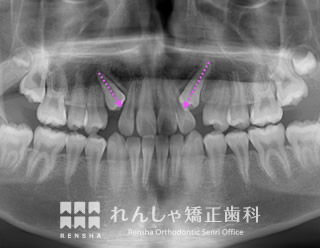

埋伏(15歳 治療期間:2年10か月)

上の犬歯が2本とも埋まったままになっていたので、スペースを確保して引っ張り出しました。

浅い位置に埋まっていたため比較的簡単に牽引することができましたが、骨の深い位置に埋まっていると治療の難易度が非常に高くなります。

| 主訴 | 上の犬歯が出てこない |

| 診断名 | Angle Class I 上顎両側犬歯の埋伏を伴う叢生 |

| 初診時年齢 | 15歳5か月 |

| 装置名 | マルチブラケット装置 |

| 抜歯非抜歯 | 非抜歯 |

| 治療期間 | 2年10か月 |

| 費用の目安 | 約89万円+消費税(検査料金、都度の処置費用等も合わせた総額) |

| リスク副作用 | 歯の移動に伴う軽微な歯根吸収、歯槽骨吸収、歯肉退縮(いずれも本症例ではほぼ無し)、矯正器具装着中のカリエスリスク増大(本症例ではカリエス発生無し) |